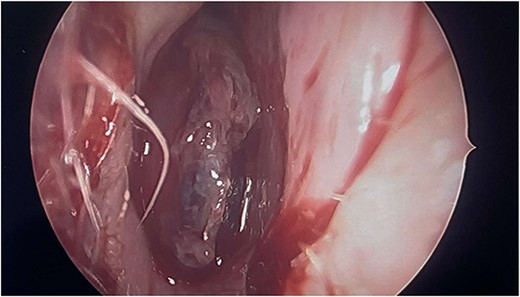

Intraoperatively, the right nasal mass appeared hyper vascular (Fig. 3) and bled easily with manipulation. After adequate anesthesia, a zero-degree endoscope and microdebrider were used to take down the right nasal cavity mass. Significant bleeding was encountered during extirpation. The bleeding was successfully stopped via cauterization with suction Bovie and bipolar cautery and topical adrenaline application. Hemostatic packing was placed into the right nasal cavity in order to ensure ongoing hemostasis. At this time, it was determined to no longer be safe to continue the procedure as the patient had lost almost 350 cc of blood and there was concern for recurrent hemorrhage with further manipulation. The decision was made to terminate the procedure and to await biopsy results of the mass prior to further attempts at resection.